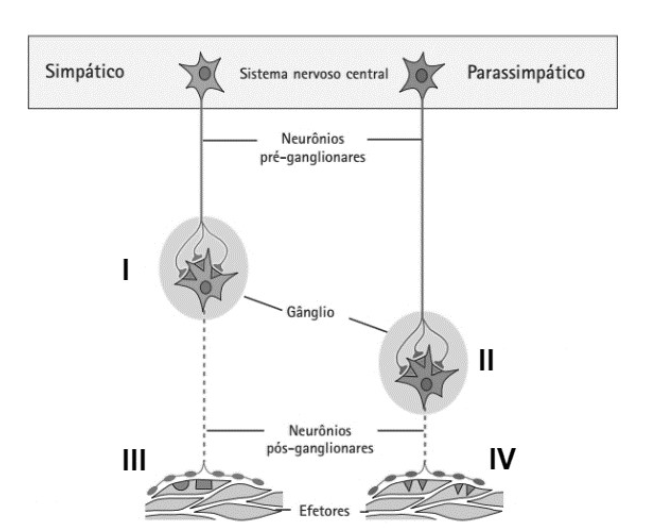

O Sistema Nervoso Autônomo, (SNA), é responsável pelo controle nervoso de determinadas funções vegetativas, principalmente, das funções circulatórias, do trato gastrointestinal, do metabolismo e das funções genitais. Os neurônios do SNA estão dispostos de acordo com a figura.

Fonte: Maurer, Martin H. Fisiologia Humana Ilustrada (2nd edição). Editora Manole, 2014.

É sabido que o SNA é influenciado pela disposição dos neurônios, tipos de neurotransmissores e de receptores ganglionares. De acordo com ilustração, assinale a alternativa incorreta.